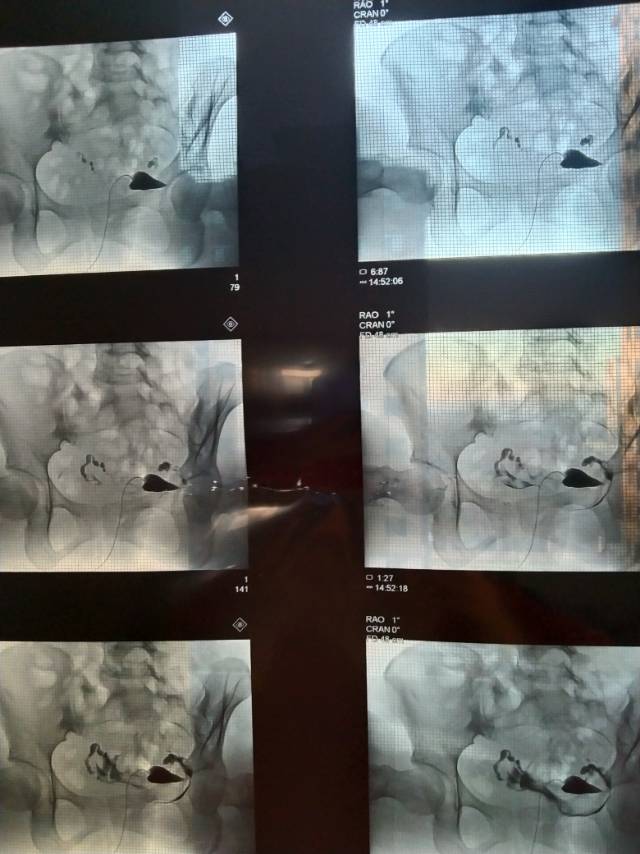

做完输卵管造影第六天了小腹还是感觉沉甸甸的如

可以热敷腹部,如果有发热,腹痛加剧,白带量多,有异味,随时就医